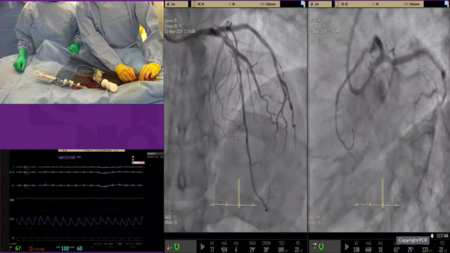

Complex multivessel disease - LIVE Case

An 89-year-old male patient presented with stable angina, preserved LV function and some risk factors such as hypertension and diabetes. CT scan and angiography revealed occlusion of proximal RCA and bifurcation lesions on LAD and circumflex (medina 1,1,1). Operators treated the bifurcation lesions with provisional stenting.